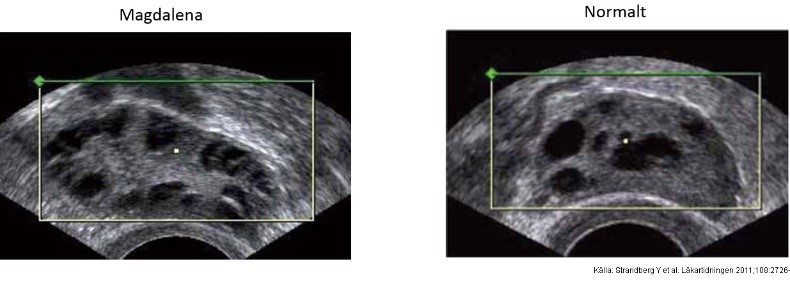

Magdalena söker vid 39 års ålder för mellanblödningar och postkoitala (efter samlag) blödningar. Postkoitala blödningar ska alltid föranleda misstanke om

A

Cervixcancer

• Ung kvinna (18 år) inkommer till vårdcentral. Ej haft menstruationer på 6 mån, gravtest negativt. Ökad behåring på käklinjen samt fått mer acne på slutet. Lätt överviktig. Prover visar normal TSH, LH, FSH, fP-glukos, östradiol och testosteron. Högt insulin, sänkta nivåer av SHBG, förhöjd testosteron/SHBG-kvot

• Fler än 12 små antralfolliklar (<8 mm vardera) per ovarie.

Vilka kriterier för PCOS uppfyller Magdalena?

• Oligomenorré/amonerré

• Kliniska och/eller biokemiska tecken på hyperandrogenism

• Polycystiska ovarier